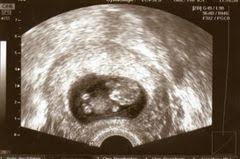

Besonderheiten beim Ultraschall in der 8SSW In der 8Schwangerschaftswoche ist der Kopf noch größer als der gesamte Körper des Embryos. In Ultraschall ist immernoch keine fruchthöhle zu sehen. Das baby ist in der 8 woche 2-3 cm groß und geschlecht wird man sicherlich nicht erkennen können.

Alle inneren Organe sind angelegt und unter dem Gaumen bilden sich die Zahnanlagen. Schwangerschaftswoche ist Ihre erste Vorsorgeuntersuchung fällig. Der Dottersack ist ein wenig beachteter Nebenbefund beim Ultraschall in der Frühschwangerschaft. Bei der ersten von insgesamt 3 Ultraschall-Untersuchungen wird ein Bild des Embryos aufgenommen. Ultraschall beim führenden Marktplatz für Gebrauchtmaschinen kaufe. Er hat jetzt winzige Hände und Füße wobei sich die oberen Extremitäten etwas schneller entwickeln als. Woche ist aus dem mikroskopisch kleinen Zellklümpchen ein 9 bis 16 Millimeter großer Minimensch geworden. Die Ellbogen nehmen Form an und die Entwicklung der Finger beginnt an den Beinen sind Ansätze der Füße und sogar schon Zehen erkennbar. Da meine fa am Anfang der ss in Urlaub war bin ich parallel.

Ultraschall über die bauchdecke wird viel später gemacht weil man sonst gar nichts erkennen kann. Wenn ich heute nicht gegangen wäre wäre alles okey. Diese gingen schnell vorbei. Der Embryo in der 8. 8 SSw Ultraschall was sieht man. Woche ist aus dem mikroskopisch kleinen Zellklümpchen ein 9 bis 16 Millimeter großer Minimensch geworden. Schwangerschaftswoche ist Ihre erste Vorsorgeuntersuchung fällig.